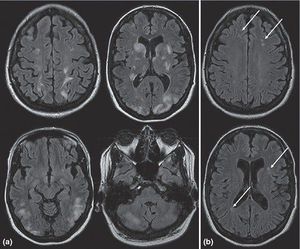

A 21-year-old primigravida is brought to the emergency department after suffering from a generalized tonic-clonic seizure at 32 weeks’ gestation. The seizure was preceded by a severe headache. She lost control of her bowels and bladder. She has gained 10 pounds since her last prenatal visit 2 weeks ago. On examination she is unresponsive and in a postictal state. Her BP is 185/115, and a spot urine dipstick shows 4+ protein. whats your DX? #medicina #anatomia #corpohumano #transplantedecórnea #inflamação #cirurgia #oftalmologia #Brasil #residência #hospital #enfermagem #biologia #medical #surgery #eye #cornealtransplant #surgeon #science #brazil #health #anatomy #medstudent #biology #opthamology #nurse #surgery #operation #eye #premed #medstudent #premed #premedlife #pus #infection